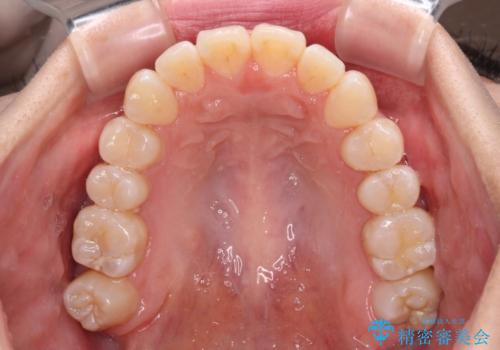

外に飛び出して磨きにくい奥歯と上下前歯の隙間 インビザラインによる矯正治療

- 上下前歯の隙間と、外側を向いていて歯磨きのしにくい奥歯を気にして来院された患者様です。

下顎前歯が1本欠損しており、上下アーチはアンバランスとなりますが、インビザラインを用いて上下の隙間を改善しながら歯列を整えることとしました。

外側を向いている奥歯は、内側にアンカースクリューを埋入して牽引の固定ゲント氏、部分的にワイヤー装置を用いることで歯列に納めることとしました。